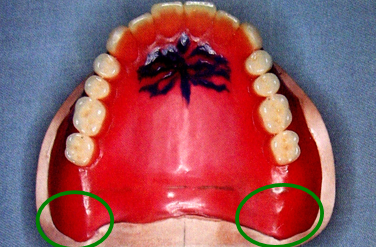

8.腭小凹(palatal fovea)

口内粘液腺导管的开口,位于上腭中缝后部的两侧。

上颌全口义齿的后缘应在腭小凹后2mm处 ,颤动线位于腭小凹的稍前部。

10.颤动线(vibrating line)

位于软腭与硬腭的交界部位。发“啊”音时软腭升高,发音结束后又复归原位,故又称“啊”线。

堵住鼻孔用鼻子出气会使软腭向下降,能明确观察到颤动线。

该线通常作为决定义齿基托后缘的标志,分前、后颤动线,两者之间为后堤区,宽约2~12mm 。

⑤后堤区: 腭小凹后方,轻压颤动线以获得良好的封闭。